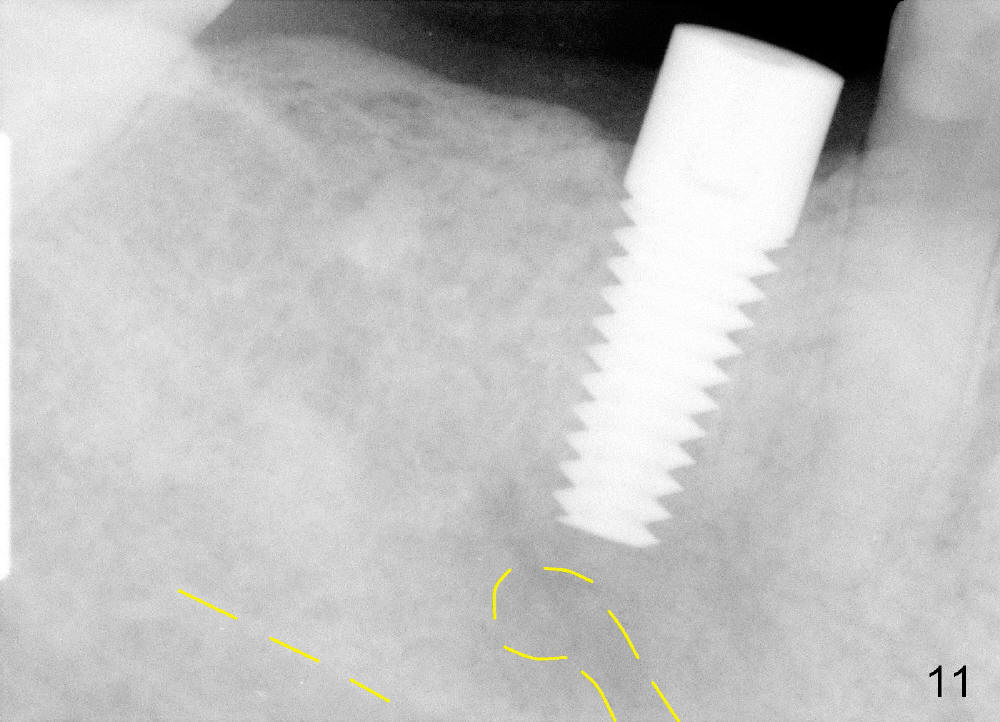

The implant appears to be osteointegrated 4 months postop (Fig.11). A healing cuff is inserted in preparation for restoration 2-4 weeks later (Fig.12). Fig.13 shows that the crown is just cemented. One month later, the patient is concerned about the metal showing through the gingiva (*). To overcome the issue, gold coated implant is used, an implant is placed more lingual (smaller), or bone graft is placed buccal to the implant. There is no bone loss 3 years 5 months post cementation (Fig.14).